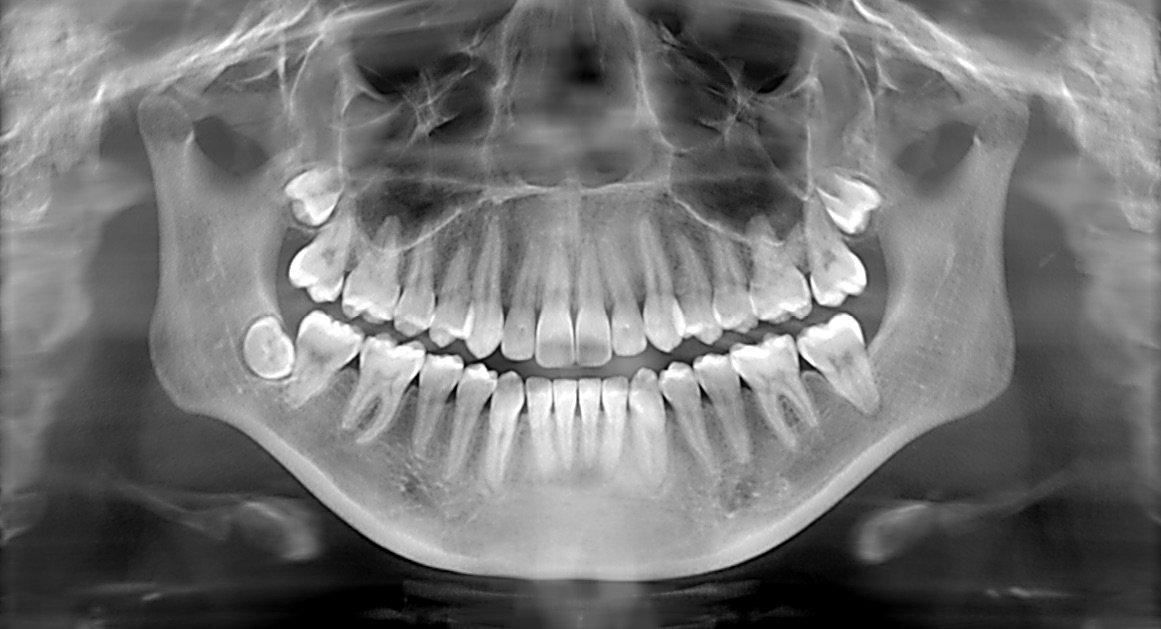

Panoramic X-rays show the entire mouth area all the teeth in both the upper and lower jaws on a single X-ray. This X-ray detects the position of fully emerged as well as emerging teeth, can see impacted teeth and helps diagnosis tumours.